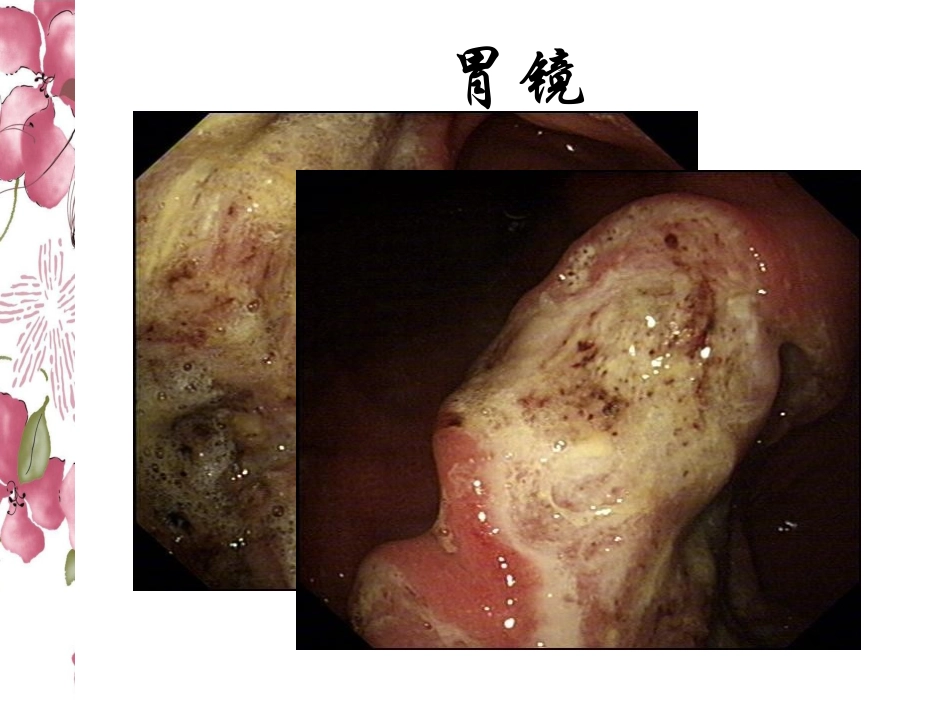

腹组病例汇报2012-6-12MedicalHistory•Male,51yearsold,rapidemaciationfortwomonths,Epigastricdiscomfort胃镜腹部强化CT淋巴瘤•淋巴瘤(lymphoma):起源于淋巴结和淋巴组织,其发生大多与免疫应答过程中淋巴细胞增殖分化产生的某种免疫细胞恶变有关,是免疫系统的恶性肿瘤•按组织病理学改变,分为霍奇金淋巴瘤(Hodgkinlymphoma,HL)和非霍奇金淋巴瘤(nonHodgkinlymphoma,NHL)HL与NHL的不同HLNHL发病年龄青年多见随年龄增长,发病增多原发部位一个或一组淋巴结随机和不确定性(约2/3原发于淋巴结,1/3原发于结外器官)扩散类型邻近淋巴结转移不连续性,有远处扩散和结外侵犯的倾向组织学分类较简单非常复杂RS细胞含有无临床表现首发症状主要为无痛性颈部或锁骨上淋巴结进行性肿大,发热、盗汗、瘙痒及消瘦等全身症状较多见,特有表现为饮酒后淋巴结疼痛(非所有患者都有)复杂,为无痛性颈部或锁骨上淋巴结进行性肿大为首发症状的较前者少见,常以高热、各器官及系统症状为主要临床表现经典RS(Reed-Sternberg)细胞•经典的RS细胞为镜影细胞,两个核相对排列,彼此对称,每个核都有一个大包涵体样嗜酸性核仁,周围有透明带,两个核看起来似猫头鹰的双眼,核膜明显•典型的RS细胞最常见于混合细胞型,而在结节硬化性不常见,在淋巴细胞为主型则更罕见胃淋巴瘤•按照淋巴瘤的发生部位,可将其分为淋巴结内和淋巴结外淋巴瘤•淋巴结外淋巴瘤中胃肠道是最好发的部位,约占结外淋巴瘤的50%,但只占胃恶性肿瘤的2-7%•胃淋巴瘤(gastriclymphoma)在临床上分为原发性和继发性两种•原发性胃淋巴瘤(primarygastriclymphoma,PGL)其临床病理具特异性胃壁分层胃淋巴瘤起源于粘膜下层的淋巴组织,沿胃的长轴生长病因•不完全清楚•两种学说:病毒感染学说免疫缺陷学说•MALT淋巴瘤的发病与幽门螺杆菌(helicobacterpylori,HP)感染密切相关•HP的慢性感染状态刺激了黏膜内淋巴细胞聚集,由此而引发的一系列自身免疫反应激活免疫细胞及其活性因子,造成了胃黏膜内淋巴滤泡的增生为胃淋巴瘤的发生奠定了基础MALT的发生临床表现•缺乏特异性•可以出现腹痛、上腹不适;呕血和黑便为表现的上消化道出血症状;腹部肿块纳差、消瘦、贫血;消化道梗阻症状临床诊断原发性胃淋巴瘤依据临床诊断PGL的主要依据:•(1)浅表淋巴结无肿大;(2)纵隔淋巴结无肿大;(3)白细胞计数及分类正常;(4)肝脾无异常;(5)病变以胃为主,可伴有区域淋巴结转移。•如不符合上述条件则认为是继发性胃淋巴瘤,即全身性淋巴瘤的一部分。PGL的病理类型•在2001年WHO淋巴瘤分类中,恶性淋巴瘤共分为30种病理类型•在PGL中上述病理类型均可发生,但常见的是B细胞来源的非霍奇金淋巴瘤(NHL)•PGL主要病理类型包括:弥漫性大B细胞淋巴瘤(DLBCL)(占45%~59%)、黏膜相关淋巴组织(MALT)淋巴瘤(占38%~48%)、滤泡性淋巴瘤(FL)(0.5%~2.0%)、套细胞淋巴瘤(MCL)(占1%左右)、Burkitt淋巴瘤(占1%左右)及T细胞淋巴瘤(1.5%~4.0%)等分级及分期•AnnArbor改良分期法是根据受累范围及淋巴结转移部位而设计的分期法。•ⅠE期:淋巴瘤局限在胃,无淋巴结转移ⅠE1期:肿瘤限于粘膜及粘膜下层(称早期淋巴瘤);ⅠE2期:肿瘤已穿越粘膜下层。•ⅡE期:淋巴瘤局限在胃,有淋巴结转移。ⅡE1期:胃淋巴瘤伴胃周淋巴结转移;ⅡE2期:胃淋巴瘤伴横膈下非胃周淋巴结转移。•ⅢE期:胃淋巴瘤伴横膈两侧淋巴结转移•ⅣE期:血行播散累及其他脏器或组织分级及分期•TNM分期法•T1:肿瘤浸润粘膜层或黏膜下层;•T2:肿瘤浸润肌层;•T3:肿瘤浸润及浆膜下层;•T4:肿瘤浸润穿透浆膜层;•T5:肿瘤侵犯邻近结构。•N0:无区域性淋巴结转移;•N1:胃周淋巴结转移距肿瘤边缘3cm以内;•N2:胃左动脉、肝总动脉、脾动脉及腹腔动脉旁淋巴结有转移,或胃周距肿瘤边缘3cm以外有淋巴结转移•N3:腹主动脉旁、肝十二指肠韧带淋巴结或其他腹腔内淋巴结有转移•N4:淋巴结转移范围超过N3•M0:无远处转移•M1:有远处转移分级及分期TNM分期分期TNM5年生存率(%)ⅠT1N0,N1M0100ⅡTIN2M088.9ⅢT2,T3N0,N1,N2M052.1T4,T5任何NM...